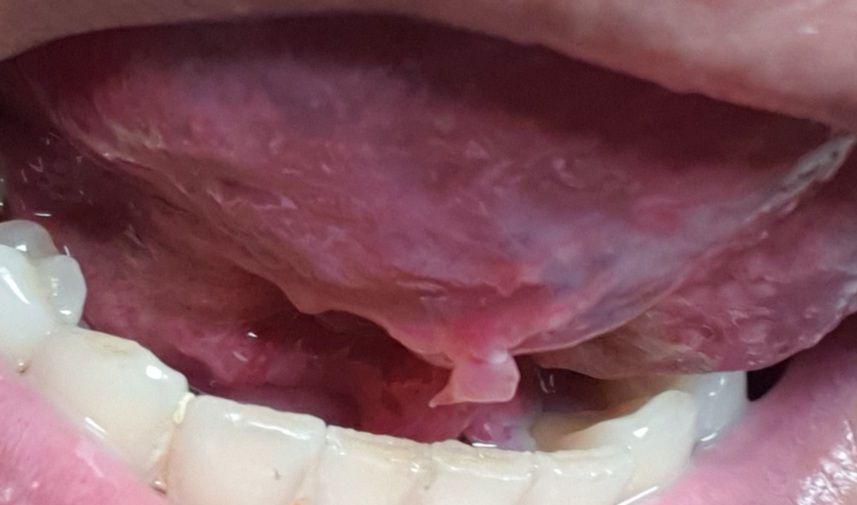

혀밑에 혓바늘인가 종기같은게 아픕니다

처음엔 잘안보여서 이물감느껴도

한이틀괜찮더니 이젠아프네요

이게 무슨종기같이 대롱대롱있어서

손가락으로 잘라낼까싶다가도

병원을가야하나 싶은데 이거 무엇인지 알려주세요

현재로서는 사진만으로 판단은 어려우며 점액종이나 섬유종을 감별하는 것이 좋겠습니다. 이비인후과에 내원하시어 진료를 받아보시는 것이 좋겠습니다.

혀 아래에 점액종이 발생한 것으로 보입니다. 시간이 경과하면 자연스럽게 사라질 것으로 보이며 특별한 처치를 하지 않아도 되겠습니다.